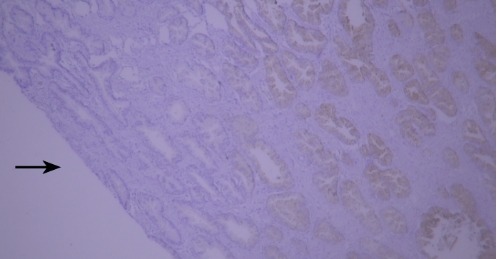

典型实例:人结肠癌石蜡组织切片CEA染色,出现染色液堆积(黑色箭头区域)。

解决建议:实验过程中需保证充分洗涤,避免染色液残留导致结果异常。